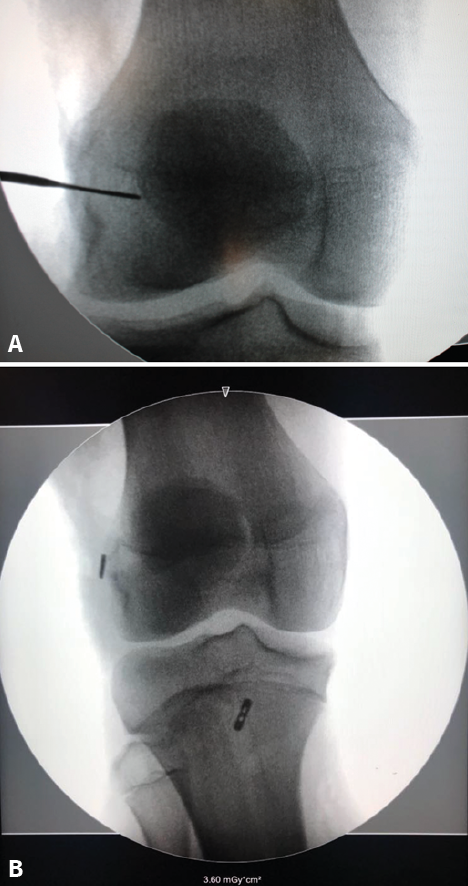

Techniques that perforate the growth physis (transphyseal techniques)

Tunnels are perforated in both physes (femur and tibia) in these techniques (Figure 5 C and D). These procedures are similar to those used in adults. The partial transphyseal technique is a hybrid procedure in which only one of the physes is tunnelled - normally the proximal tibial physis (Figure 6A). Since the tibial tunnel lies more perpendicular to the physis, the affected area is smaller, and the possible impact is considered to be minimal. Milewsky and Nissen(75) published their hybrid technique with good outcomes, though the patients presented dysmetria (1.2 and 2.2 cm). In a series of 24 patients, Chambers(76) reported four cases of physeal lesions and concluded that the procedure should be avoided in the youngest patients (Figure 6B).

Figure 6. Intraoperative radioscopic view of a reconstruction of the anterior cruciate ligament (ACL) in a skeletally immature patient with the partial transphyseal technique. A: the entry point of the femoral tunnel distal to the physis is marked by a metal tip; B: postoperative control of the partial transphyseal technique, showing the cortical button of the femur in the distal femoral epiphysis and the tibial button located distal to the physis, in a more central location, to perform a more vertical tunnel and reduce physeal damage.